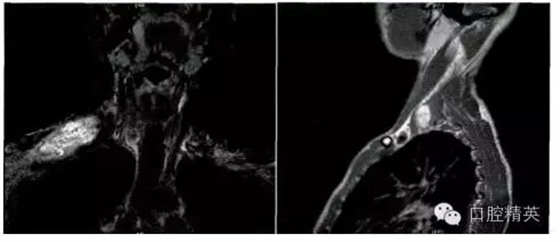

影像學檢查:頸部MRI(平掃+增強)提示右肩部鎖骨上區(qū)皮下軟組織內一巨大腫物,大小約6.1 cm×2.8 cm,其內信號不均勻,T1W1為等信號,T2W2為混雜高信號,考慮神經源性腫瘤,右側臂叢神經可疑受累(圖1)。臨床初步診斷為“右頸神經鞘瘤”。

圖1.頸部MRI示右鎖骨上區(qū)皮下軟組織內一巨大腫物